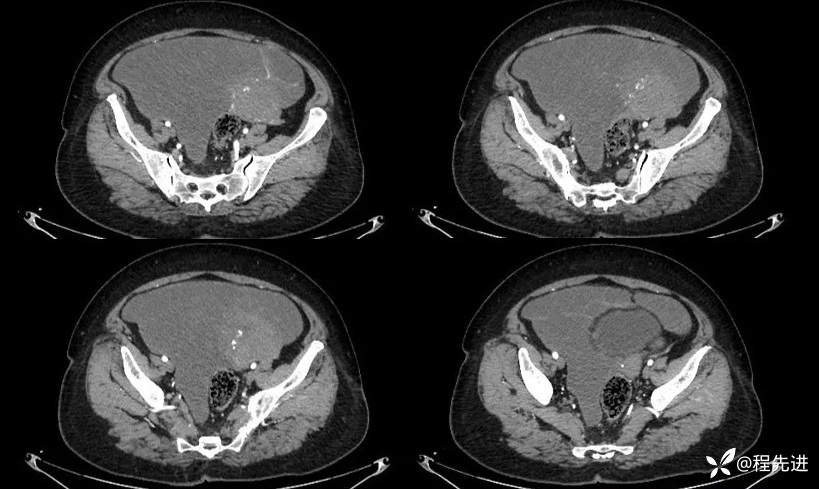

延迟期: